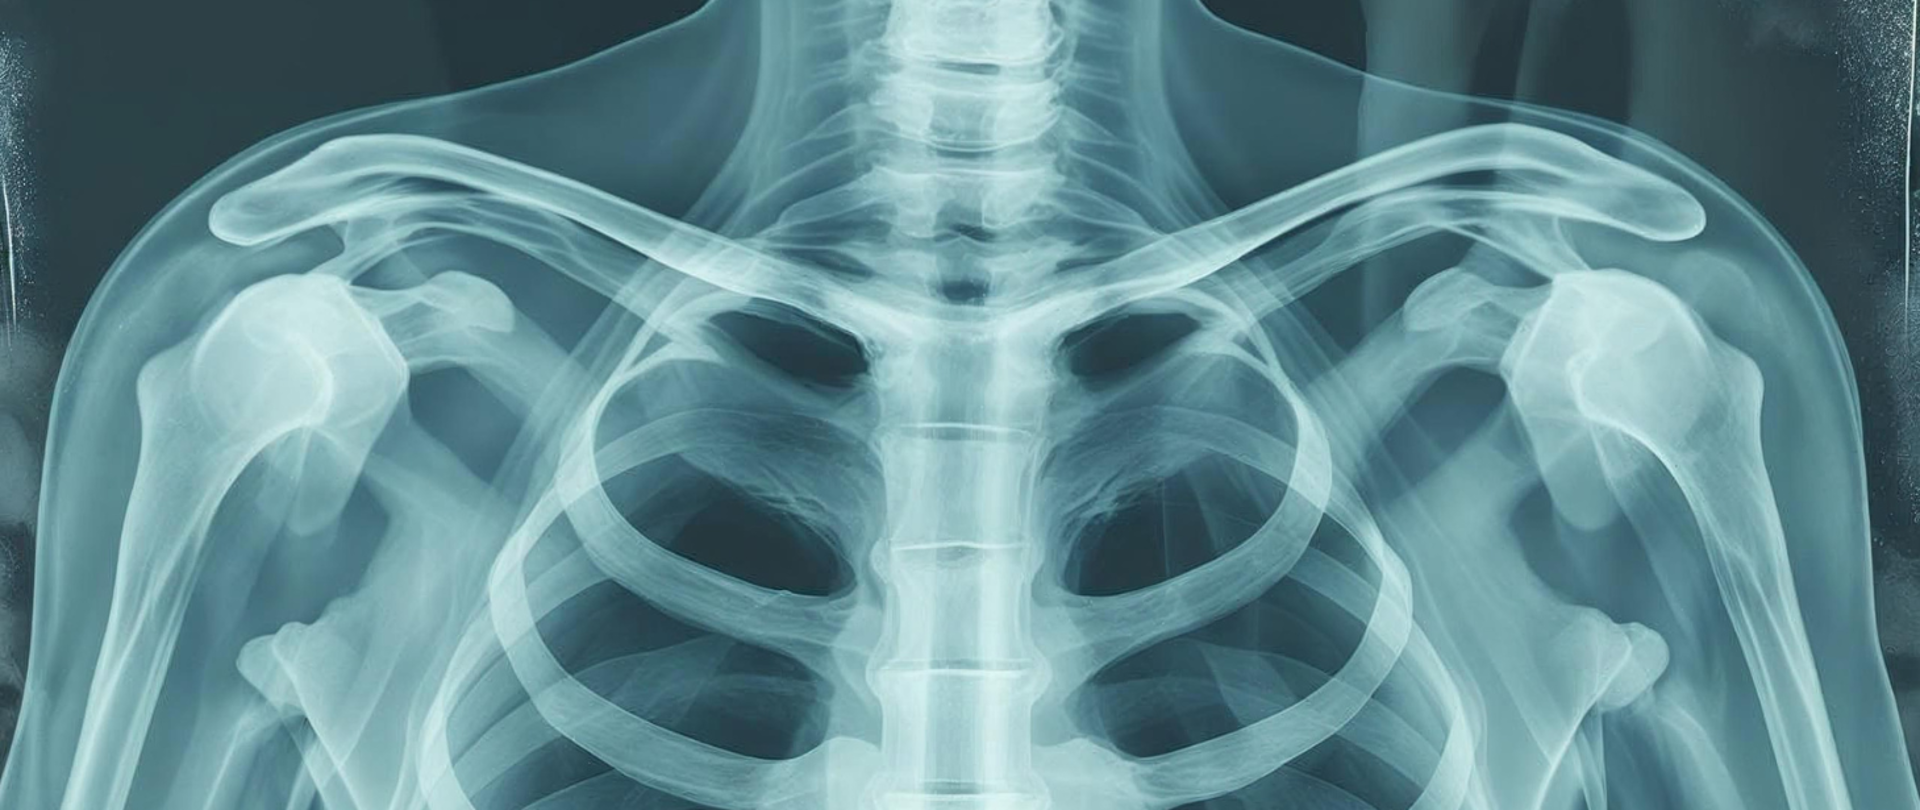

zdjęcie rentgenowskie klatki piersiowej

8 listopada każdego roku, na pamiątkę odkrycia w 1895 promieniowania rentgenowskiego, obchodzony jest Światowy Dzień Radiologii.